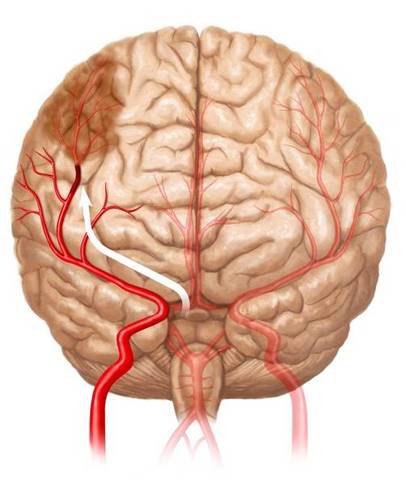

Necrosis Laminar

Tiene lugar en regiones irrigadas por las arterias penetrantes.

-La sustancia gris de la corteza esta irrigada por este tipo de arterias que van a dar lugar a una red capilar.

-Un descenso brusco de la presión arterial reduce significativamente el flujo sanguíneo a lo largo de esto conductos capilares.

-La necrosis resultante es de tipo laminar y compromete en mayor medida las capas mas profundas de la corteza cerebral.